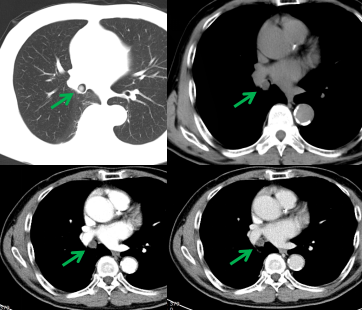

老年男性,體檢胸部CT檢查發(fā)現(xiàn)右肺中間段支氣管及右肺中葉支氣管不通暢,右肺中葉肺不張,右肺下葉炎癥。患者無咳嗽、咳痰、胸悶、氣短、咯血等不適,飲食、睡眠可,大小便無異常,近期體重無明顯下降。既往有“高血壓”“心臟早搏”病史,吸煙30余年,每日1包,無飲酒嗜好。腫瘤標志物無明顯異常。完善胸部強化CT檢查提示支氣管腔內(nèi)腫瘤,建議支氣管鏡檢查(圖1)。

圖1,右肺中間段支氣管結(jié)節(jié)(綠箭),增強掃描輕度強化。